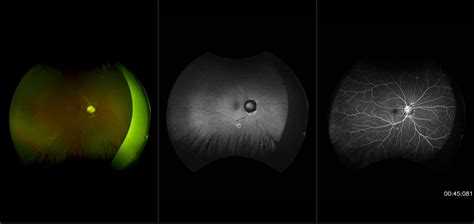

Morning Glory Syndrome, also known as morning glory disc anomaly, is a rare, unilateral—though sometimes bilateral—congenital defect of the optic nerve. It is named for its striking visual resemblance to the morning glory flower. In a healthy eye, the optic nerve head is typically pink, oval, or circular with a clearly defined rim. In contrast, an eye affected by this syndrome presents with an enlarged, excavated, funnel-shaped depression that disrupts the normal anatomy of the optic nerve.

• Excavated optic disc: A deep, white, or yellowish depression at the site where the optic nerve meets the retina.

• Peripapillary halo: A ring of depigmented, raised tissue surrounding the optic nerve head.

• Vascular abnormality: The retinal blood vessels typically emerge from the periphery of the disc rather than the center, appearing straightened and radiating outward like the spokes of a wheel.

• Central glial tuft: A white, grayish mass of tissue often sitting in the center of the excavation.

• Ophthalmoscopy: Direct visualization of the retina to identify the characteristic "flower-like" shape of the disc.

• B-Scan Ultrasonography: Useful for confirming the posterior excavation and ruling out other conditions like staphyloma.

The risk of retinal detachment is perhaps the most significant ocular concern. Due to the anatomical weakness in the area surrounding the optic disc, patients are at a higher risk of developing serous retinal detachments. Regular follow-up appointments with a retinal specialist are necessary to monitor any changes in the retina that might necessitate intervention.